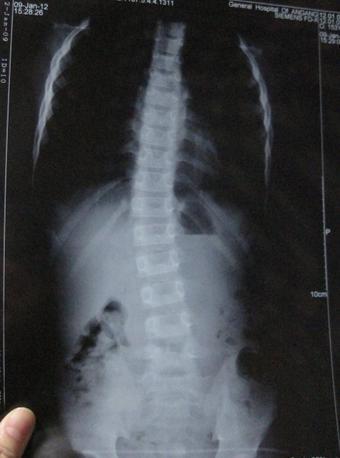

2012年7月,刚刚拿到大学录取通知书的他却出现下腰背部疼痛现象,特别是一旦遇到温度突然下降的时候,双侧髋关节疼痛为重,夜间睡觉腰背发僵,翻身困难,到当地医院检查;X线示:双侧髋关节间隙狭窄,HLA-B27(+),血沉43mm/h,诊断为:强直性脊柱炎,因为着急到校报到,未坚持系统用药治疗,病情逐渐加重,至行走困难。

(图:X线片显示季先生脊柱已经成中度弯曲)